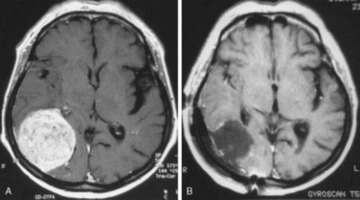

Beyin Metastazı Belirtileri ve Tedavisi